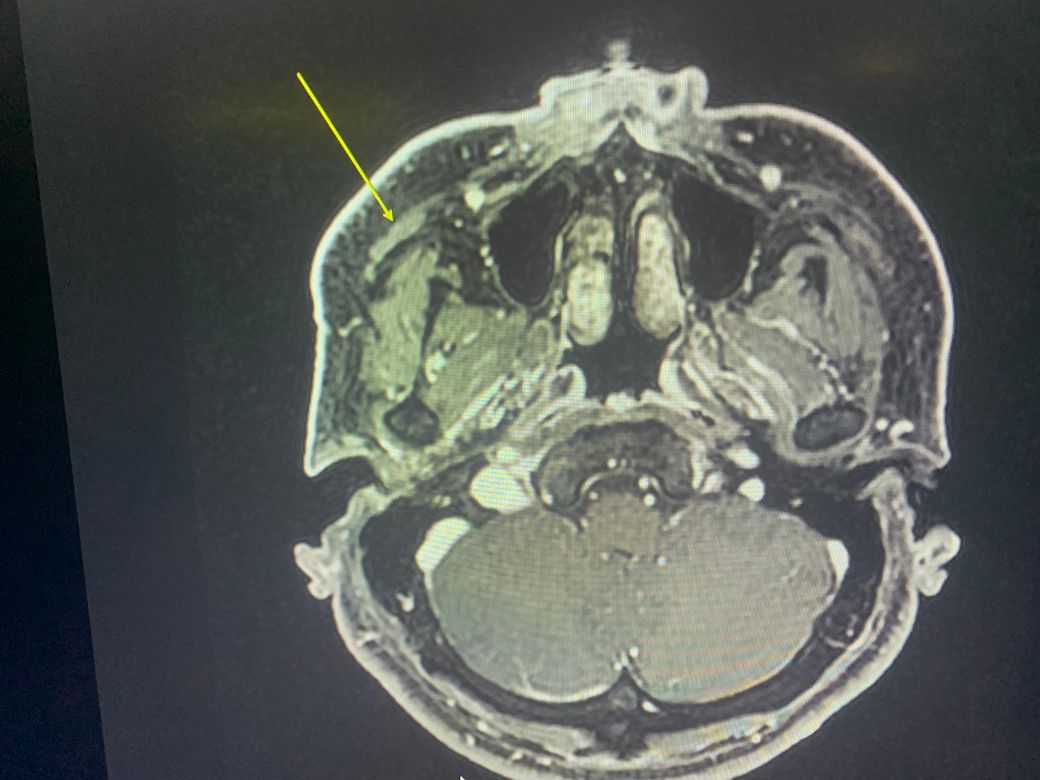

Mri좀 봐주세요 광대뼈아래에 큰소리가 났습니다 소리난 후로 앞광대주변으로 통증이 있어서 mri를 찍었는데 저렇게 하얗게 나왔는데요. 수술로 치료가 가능할까요.

오육년전에 앞광대 바로 아래에서 뭐가 부러지는소리가 나고 지금까지 얼굴에 계속 부종 통증이 있습니다

• 3번 째 사진